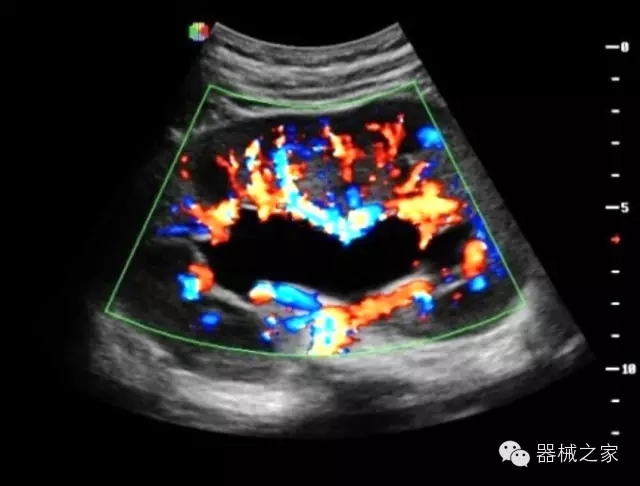

·智能微血流成像技術(shù):智能微血流捕捉技術(shù)可以提取出隱藏在背景噪聲中的弱血流信號,大大提高低速血流的敏感性;

超聲科常規(guī)領(lǐng)域應(yīng)用

·移植S40高端臺式彩超高端平臺技術(shù),滿足超聲科腹部、淺表、婦產(chǎn)科、心血管、肌骨等應(yīng)用,提供超聲科完美解決方案;